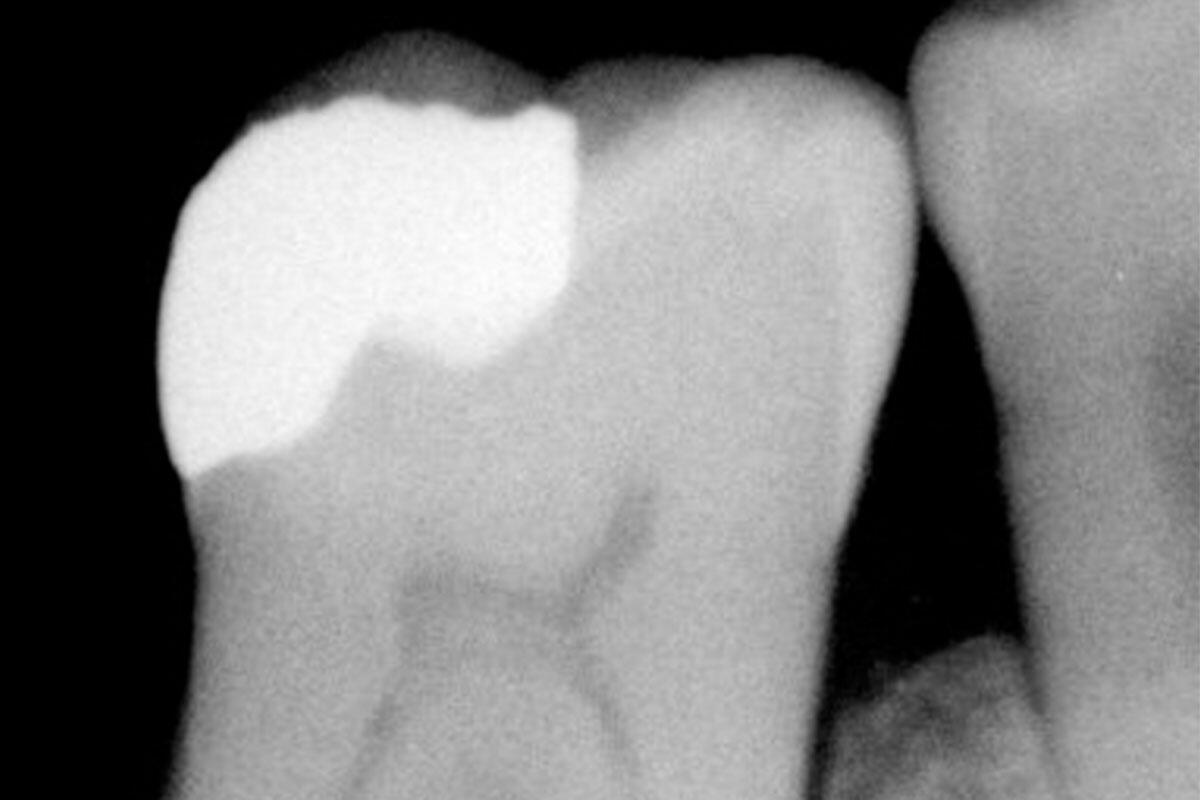

In ambito odontoiatrico infatti il mercurio non viene usato puro, vista la sua proprietà di restare allo stato liquido a temperatura ambiente, ma attraverso leghe con altri metalli fra cui argento e rame. All’origine del suo successo nell’applicazione come amalgama per otturazioni, oltre al costo contenuto, c’è anche la facilità di manipolazione, riempendo interstizi e fessurazioni per riparare i denti. Inoltre è un materiale che dura a lungo: «Ho visto otturazioni superare anche i 40 anni di applicazione – racconta il dottor Nicolin – l’inconveniente principale resta l’estetica, che accosta al bianco dei denti tracce sulla tinta del grigio che si notano in bocca».

«L’amalgama ha il grosso vantaggio di non temere l’ambiente umido della bocca oltre ad avere proprietà batteriostatiche, che non fanno proliferare i batteri, ad esempio per applicazioni a livello del margine gengivale è ancora molto performante, oggi però ci sono valide alternative – conclude Nicolin – già dagli anni ’90 sono arrivati sul mercato prodotti a base di compositi in resina, che uniscono alla facilità di manipolazione l’aspetto estetico rendendo le otturazioni quasi impercettibili, ovviamente costano di più».